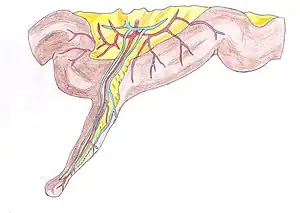

- Meckel's diverticulum, a persistent portion of the omphalomesenteric duct, is present in 2% of the population,[10] making it the most common congenital gastrointestinal malformation.[11]

Meckel's diverticulum

Meckel's diverticulum Large bowel (sigmoid colon) showing multiple diverticula: the diverticula appear on either side of the longitudinal muscle bundle (taenium).